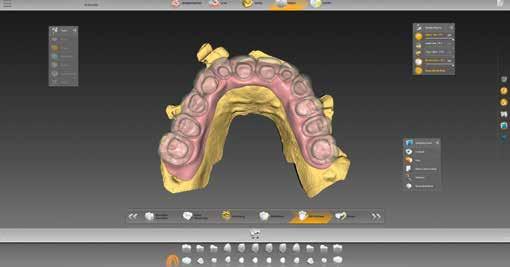

1–2. ábrák: A BioCopy és a felső állcsont beolvasása.

szükséges információ rögzítésére megfelelt. A meglévő pótlásról is készült egy ún. BioCopy-Scan (1. ábra), amelyet összevetíthetünk a felső állcsontról készült, az adhezív sapkákat is tartalmazó beolvasással (Atlantis Conus Abutment, Dentsply Sirona). Így meghatározhattuk a vesztibuláris szituációt és a vertikális helyzetet, ami megkönnyíti a funkcionális és esztétikai szempontból is kiemelkedő munka elkészítését. Ellenőriztük a meglévő pótlás egyensúlyát és érintkezési pontjait (3–4. ábrák), meghatároztuk a minta tengelyét (5. ábra), majd az adatokat az inLab szoftverbe importáltuk.

Tervezés az inLab szoftverrel

A tényleges munkát megelőzte a restauráció típusának kiválasztása. Kipipáltuk a multilayer és gingiva szavakat (6. ábra). Ezenfelül három hidat (14-16, 13-23, 24-26 régió) jelöltünk be, amelyek később a tercier részek lesznek. A „Modell” munkafázisban külön-külön megnézhettük a maxilla és mandibula mintáját (7. ábra), és ellenőrizhettük az intermaxilláris távolságot (8. ábra). A BioCopy alapján pontosan állíthattuk be a két mintát egymáshoz képest (9. ábra). Ezt követte egy nagyon fontos lépés: a felső állcsont gerinc-középvonalának berajzolása (10.

9. ábra: A BioCopy szkennelés alapján illesztjük a felső és alsó mintát. 6. ábra: Az adminisztratív fázisban meghatározzuk az alapbeállításokat, aktiváljuk a „multilayer” és „gingiva” mezőket.